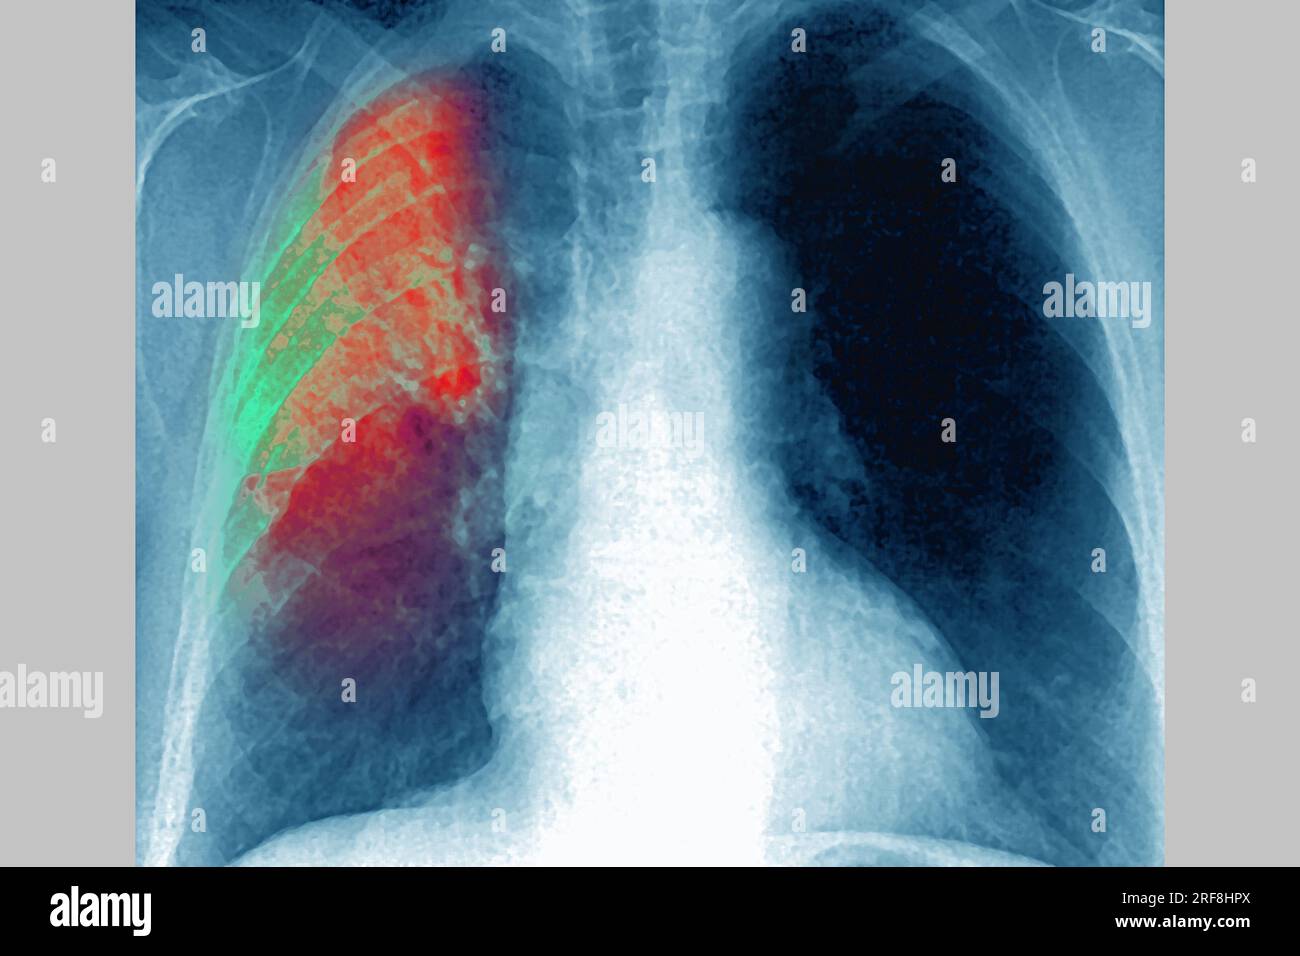

RM2RF8HPX–Pneumonie du poumon droit (infection respiratoire aiguë) révélée par une radiographie thoracique frontale.